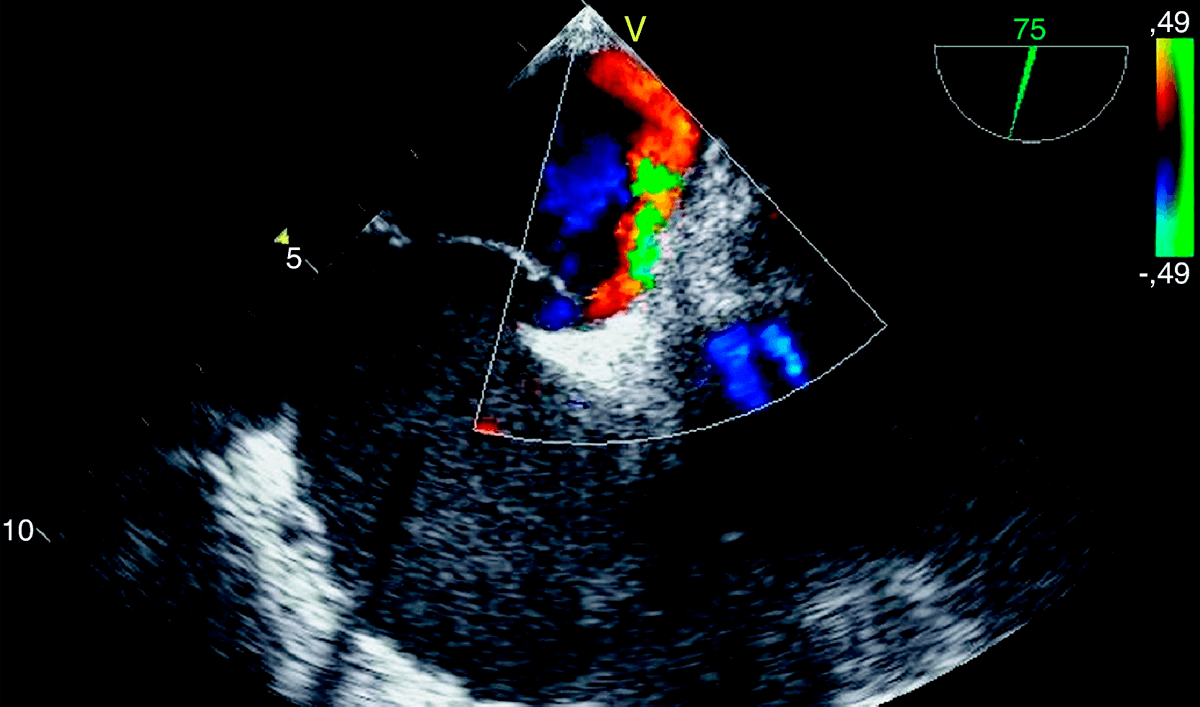

From www.scite.com.ar

Cierre endovascular de foramen oval permeable (FOP) SCITE Escala Rope Foramen Oval Permeable The risk of paradoxical embolism (rope) score helps estimate which cryptogenic stroke patients are likely to have a pathogenic. El foramen oval permeable es la causa más prevalente de ictus criptogénicos en menores de 60 años. La prevalencia de foramen oval permeable (fop) en la población general es elevada (25%). Habitualmente cursa de forma asintomática, aunque presenta un alto riesgo. Escala Rope Foramen Oval Permeable.